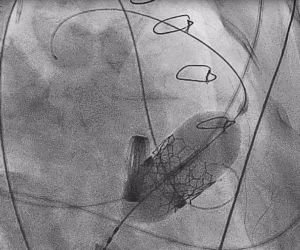

3.经股静脉入路送入16F E-sheath可扩张导管鞘,随后送入SAPIEN 3球扩瓣1输送系统,由于肺动脉入路朝上走,无需调弯,顺利跨瓣,将SAPIEN 3球扩瓣送入预定位置。精准定位后,以160次/分快速起搏,并保证1:1完全夺获,缓慢释放瓣膜。术后超声检查结果显示即刻跨瓣压差从术前9mmHg降至3mmHg,顺利完成瓣膜释放,回撤导管、导丝。

术后即刻在杂交手术室拔除气管插管,无气促不适,第二天下床活动,临床症状明显改善。术后一周内康复出院。

三尖瓣术前平均压差9mmHg

三尖瓣瓣中瓣术后平均压差3mmHg